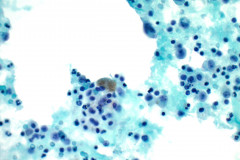

Cytology:

When reviewing the slides cytologically, there is moderate to high cellularity, with malignant cells present in three-dimensional cohesive groups as well as scattered single cells.1,7 Compared to the background population, these cells appear enlarged and demonstrate increased nuclear-to-cytoplasmic ratios, irregular nuclear borders and contours, and prominent nucleoli with variable chromatin patterns.1 Nuclear pleomorphism is present, and occasional multinucleated tumor cells can be identified.1 The cytoplasm is moderate in amount and appears vacuolated due to mucin production, which reflects glandular differentiation with extracellular mucin and necrotic debris present in the background.1,2 Overall, these cytologic findings are characteristic of an epithelial glandular cell malignancy. Because adenocarcinoma shares overlapping cytologic features with other poorly differentiated tumors, IHC stains such as TTF-1 and Napsin A are used to help confirm pulmonary origin.1,7